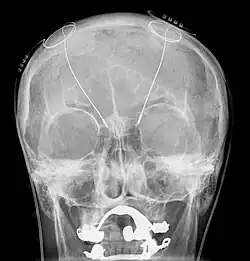

Электроэнцефалография (ЭЭГ) — один из ключевых неинвазивных методов исследования головного мозга, который характеризуется высоким временным разрешением, но низкой пространственной разрешающей способностью, особенно в сравнении с МРТ или инвазивными электродными методами. Из-за низкого пространственного разрешения (обычно не более 100 каналов), полученный сигнал является результатом суперпозиции активности крупных популяций нейронов, а значит, является удобным методом для нахождения и исследования синхронизированных коллективных режимов в сетях головного мозга. Синхронизация достаточно большой популяции нейронов обычно производит глобальные колебания, которые и записываются электродами электроэнцефалографа.

В большинстве случаев сильная глобальная синхронизация больших популяций (синхронизация типа I) присуща состоянию бездействия или патологическому состоянию, поскольку динамика полностью синхронизированной сети недостаточно сложна для эффективной обработки информации. Во время нормальной работы (кроме состояния глубокого сна) небольшие локально-синхронизированные подсети генерируют колебания разных частот (синхронизация типа II), при этом глобальная синхронизация исчезает[4]. Таким образом, спектр ЭЭГ сигнала содержит несколько важных составляющих, которые принято классифицировать по частоте, назначая каждому диапазону греческую букву. В таблице ниже приведено краткое описание каждого из ритмов согласно традиционной системе классификации, а также их соответствующие функции.